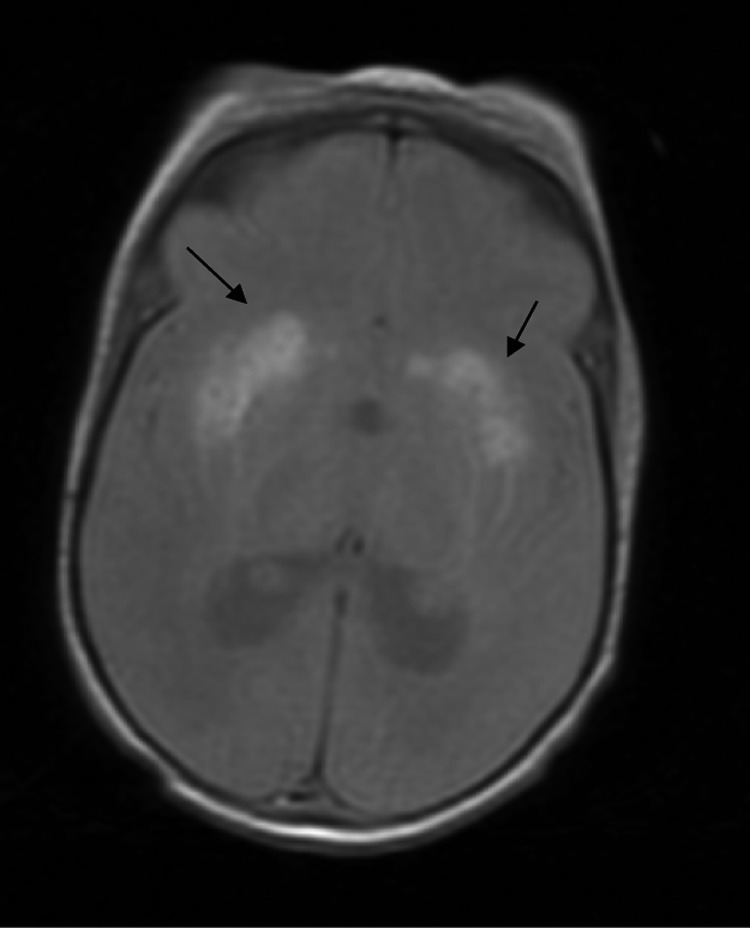

Magnetic resonance imaging showed severe impairment of the white matter (predominantly bifrontal) and a significant decrease in the grooves and ischaemic-haemorrhagia at the basal ganglia. A delay in myelination was observed. As shown in Fig. 1 (MRI axial T2 sections), we observed bilateral high intensity in the lenticular nuclei and the head of the caudate nuclei that was suggestive of haematic content.

Fig. 1.

Axial T2 section: An MRI of the brain shows bilateral high intensity in the lenticular nuclei and the head of caudate nuclei that is suggestive of haematic content (black arrows)